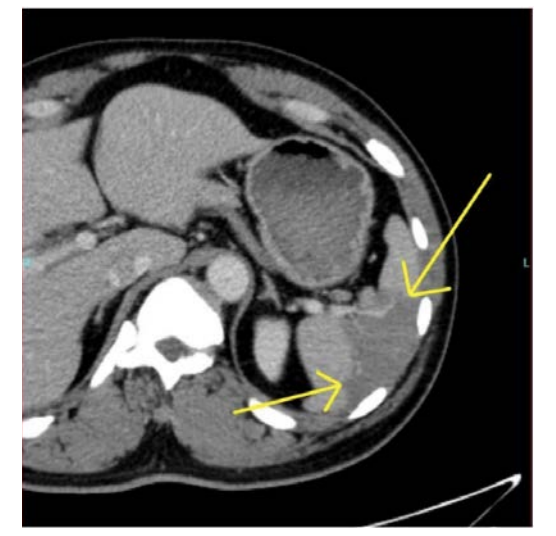

A contrast-enhanced CT scan was completed and revealed stenosis of the celiac trunk and mild bulbous dilatation of the post-stenotic celiac trunk (Figure 1). There was the appearance of a dissection flap that developed into an eccentric hypodense non-enhancing false lumen. This appeared to extend into the common hepatic arterial trunk and the splenic arterial branch, then continued to the splenic hilum (Figure 2 and Figure 3). In addition, there was a large splenic hypo-density involving almost one-third of the central spleen (Figure 4). The findings were consistent with an acute dissection of the splenic and hepatic arteries, along with splenic infarction of the central one-third of the spleen. A differential diagnosis of arcuate ligament syndrome was also considered, given the significant scoliosis seen on scout film of the CT scan (Figure 5).